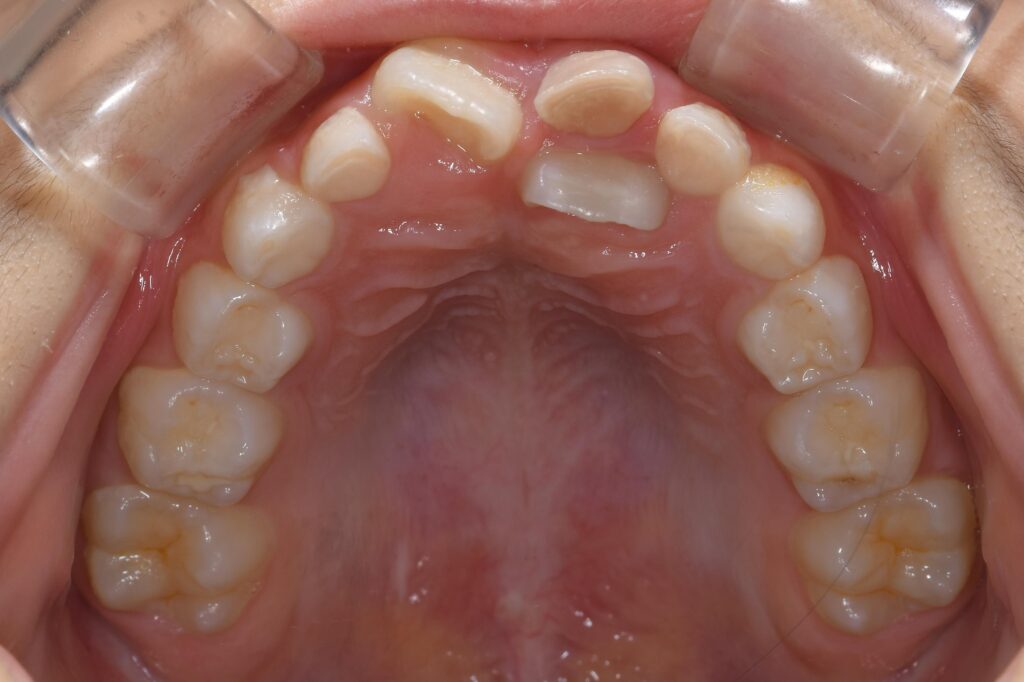

術後の写真です。

【矯正治療後】

約1か月でこのようになりました(^^)/

ちなみに歯を動かすにあたり、乳歯は抜歯しております。